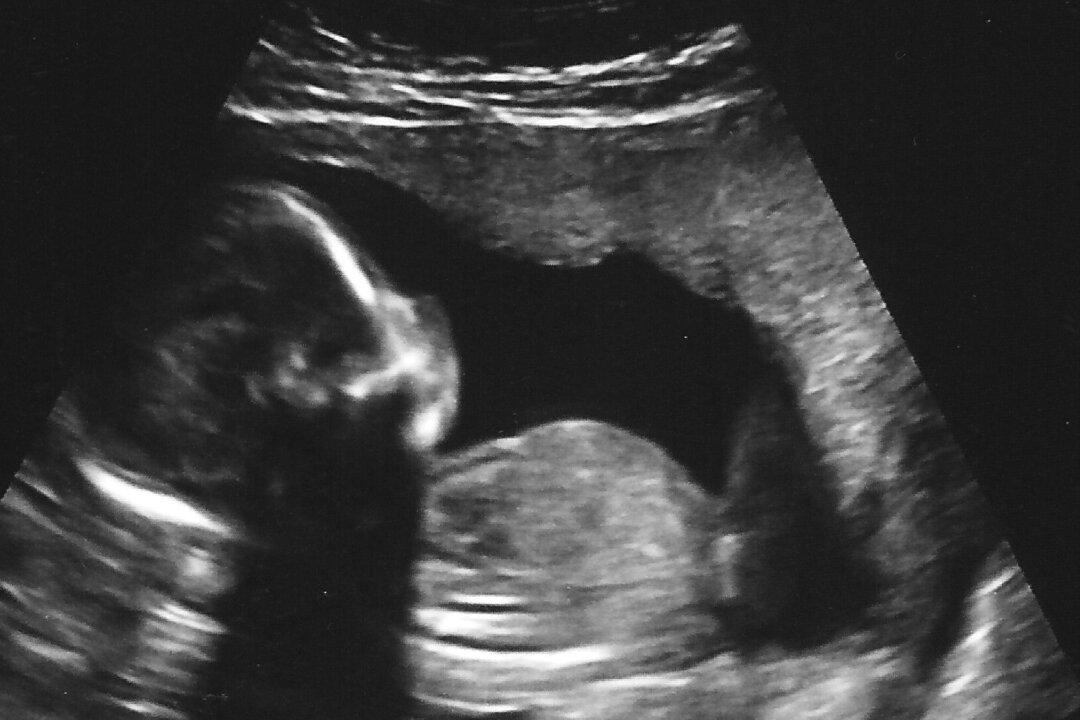

Mississippi Republican Gov. Phil Bryant, a Republican, signed a bill on March 21 that bans abortions in the state after a fetal heartbeat is detected.

That typically takes place around six weeks after conception.